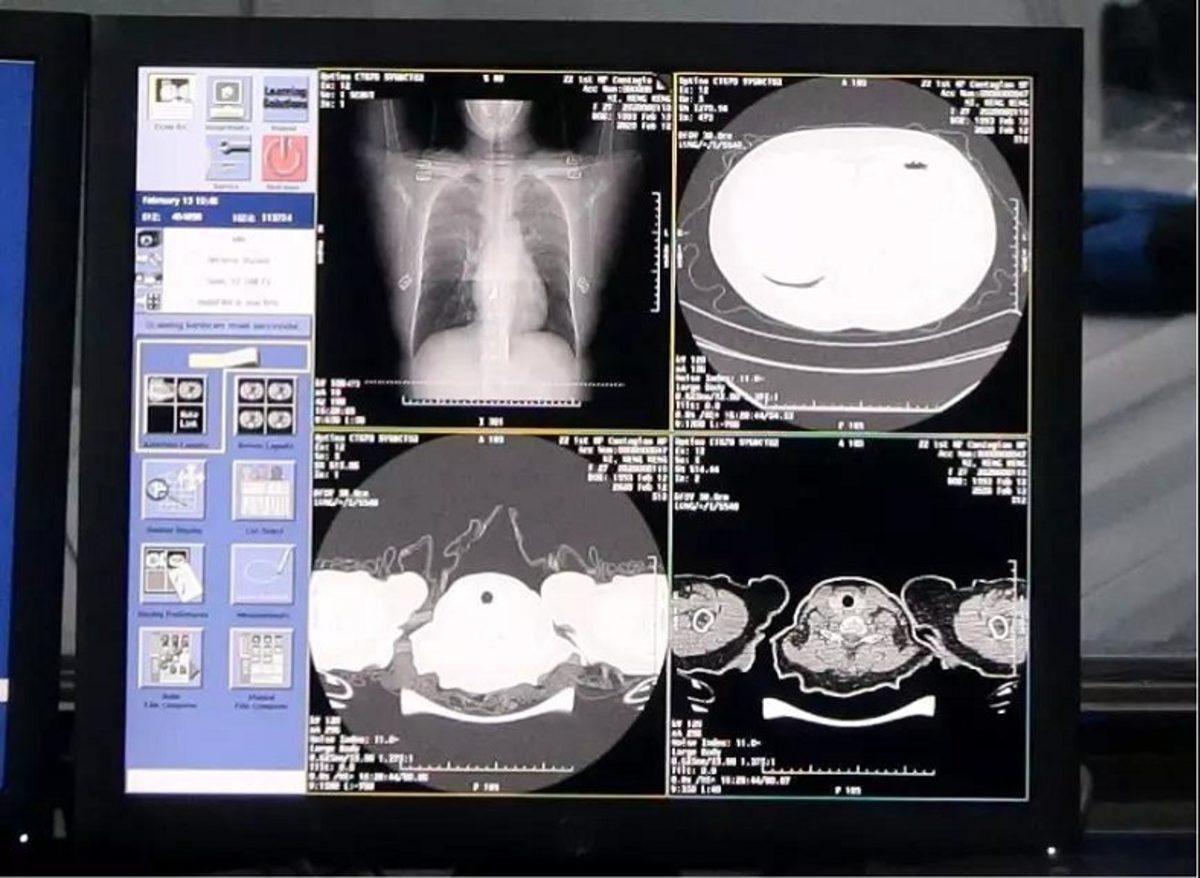

Alibaba, yeni sisteminin corona virüsünü hastaların göğüs taramalarından %96 doğrulukla tespit edebileceğini öne sürüyor. Yapay zekanın virüsü tespit etmesi sadece 20 saniye sürüyor. Normalde doktorların insanlarda hastalığı teşhis etmesi, 300'den fazla görüntüyü değerlendirmeleri nedeniyle yaklaşık 20 dakika alıyor.

Alibaba'nın sistemi, 5.000 Corona virüsü vakasından alınan görüntüler ve veriler doğrultusunda eğitildi, Çin'deki hastanelerde test edildi. Gelen bilgilere göre şu anda Alibaba'nın yapay zekası en az 100 sağlık tesisinde kullanılıyor.